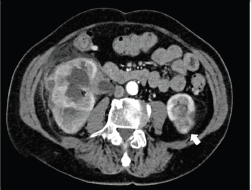

MS can also be found fortuitously during CT or PET examination in oncologic patients ([14–16]; Figure 8).

The typical appearance is of an irregular breast mass with inhomogeneous contrast enhancement and glucose uptake. On occasion, patients with MS of the breast can present other soft tissue localisation, such as the kidney (Figure 9).The histopathological diagnosis is challenging especially for the difficulties encountered distinguishing MS from lymphoma (Figures 10–12).

Figure 9. Same patient of Figure 8, showing irregular contrast-enhancing soft tissue mass (arrow), resulting in the localisation of MS.